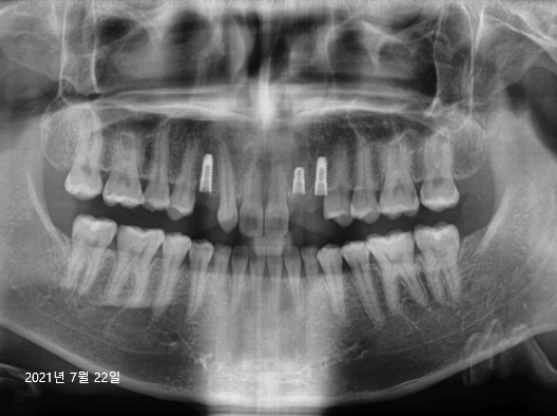

21.07.22

보다 섬세한 치료를 위해서, 컴퓨터 모의 수술을 진행해 볼 수 있는 네비게이션 임플란트를 진행하였는데요.

위 사진은 임플란트 인공치근을 식립한 (1차 수술) 후 치아 x-ray 사진입니다. 임플란트 치료에서 가장 중요한 기둥을 만들어주는 단계인 만큼, 주변 치아의 간섭 없이 올곧게 잘 식립된 모습을 확인해 보실 수 있습니다.